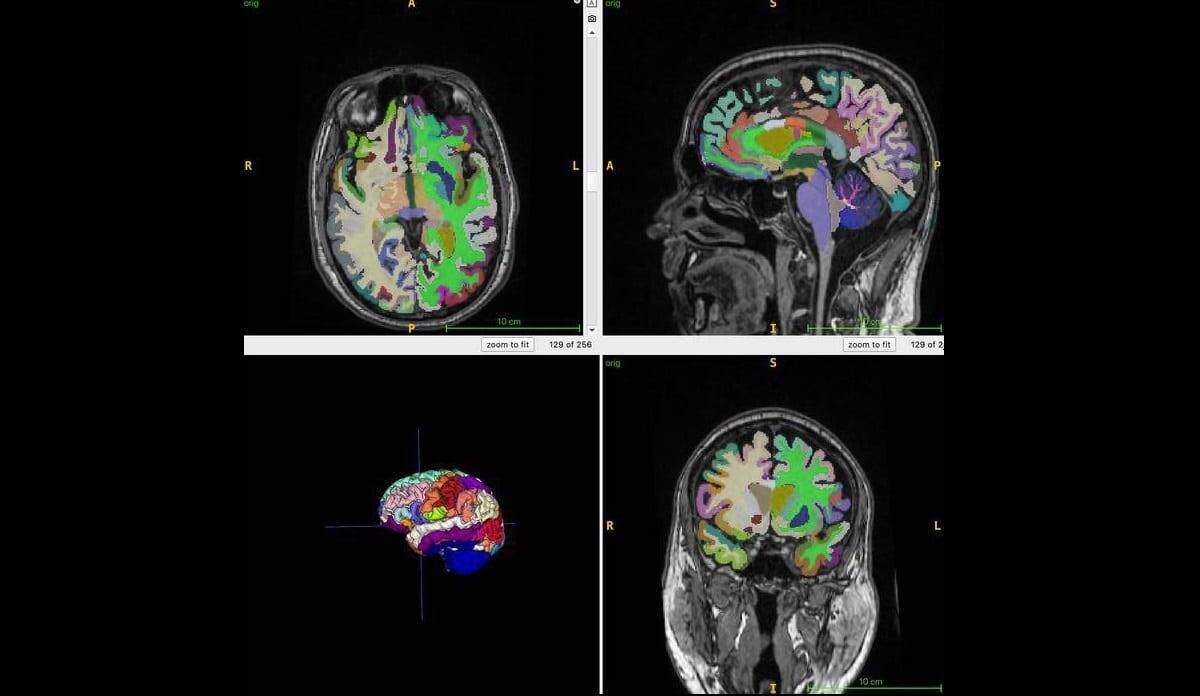

Карта мозга с цветовой кодировкой показывает пример сегментированных объемов отдельных областей, полученных с помощью объемной МРТ 3D T1. Это используется для вычислений возраста мозга с помощью искусственного интеллекта / © Cyrus Raji, RSNA